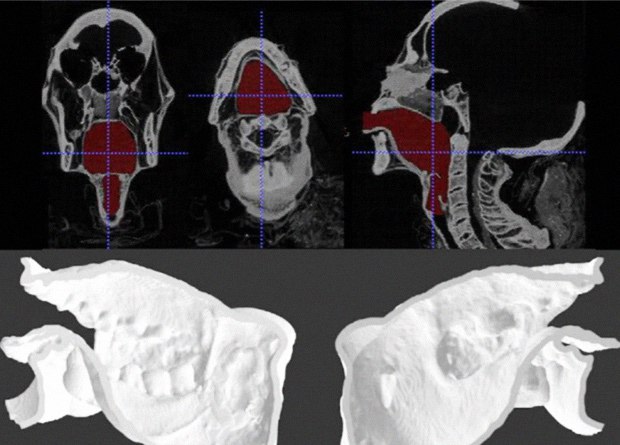

3D-печатная копия речевого тракта позволила воссоздать голос мумии древнеегипетского жреца

https://clck.ru/M37jh